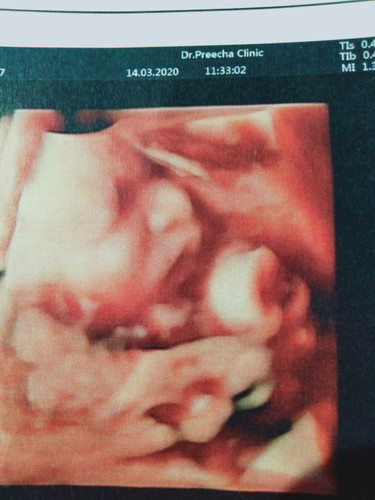

ภาพอัลตร้าซาว์ด 30 วีค น้ำหนัก 1300 รู้สึกตื่นเต้นมาก